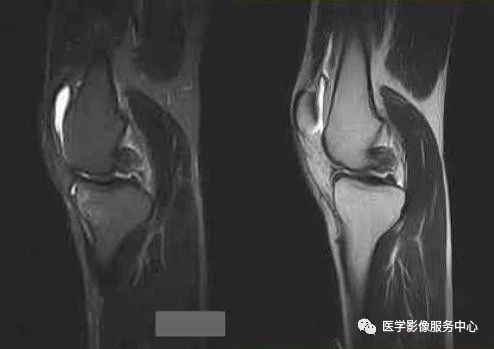

4、桶柄状撕裂

为纵形撕裂伴碎片向内侧移位,这种移位的片段类似于桶的柄,该型撕裂几乎累及半月板的所有部位,常易漏诊,在 MRI 上可以有多种表现,主要为半月板的宽度减小,在通过半月板体部的冠状面上未见到与对侧半月板共同构成的蝶形表现,同时可见到内移的半月板碎片位于髁间窝或交叉韧带旁,可形成双前、后交叉韧带征,这一征象在诊断半月板桶柄状撕裂中有重要意义;